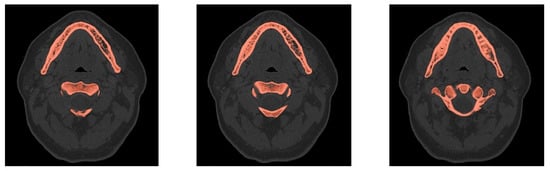

- Creation of an accurate model of the mandible together with the temporomandibular joint. The main assumption was to create a model that could be used for numerical analyses of various clinical cases, allowing the simulation of the work of fixing elements, assessment of the strength and durability of the fixation, and at the same time, without unnecessary simplifications, reflect real human anatomy. The input data were DICOM images obtained from medical imaging using computed tomography. Obtaining three-dimensional models of individual anatomical structures required the segmentation of tomographic images and then edition of the generated surface objects. Reverse engineering software for free modeling and a CAD program for parametric modeling were used.

2.2. Generation of a Three-Dimensional Model of Selected Anatomical Structures

2.3. Edition of STL Models